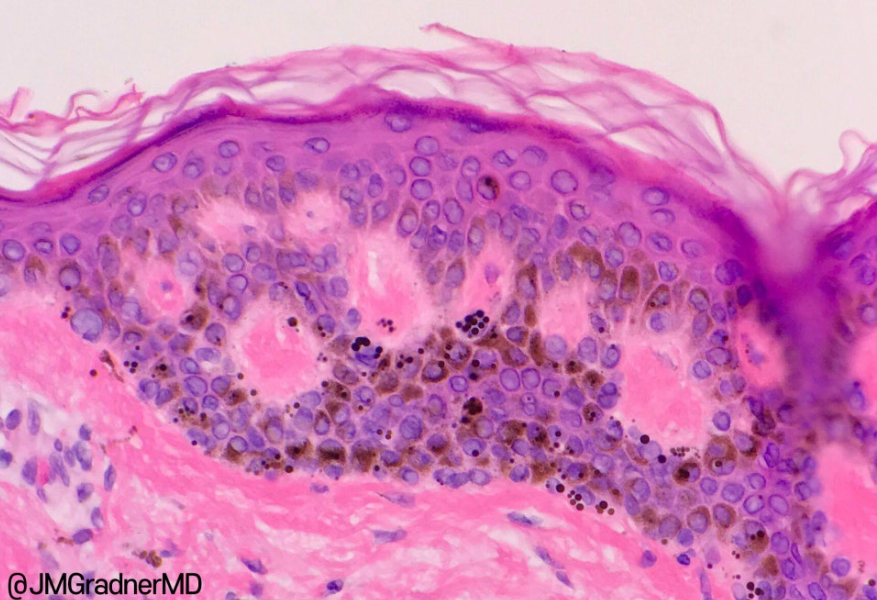

출처 : https://kikoxp.com/posts/5084/public/ 밀크커피반점(Café au lait spot) 미세현미경 관찰

밀크커피반점은 선천적으로 타고나는 갈색반점으로

멜라닌 세포가 아닌 멜라닌 색소가 과다하게

생성되어 나타나는 증상입니다.

그러다 보니 시간이 갈수록 점점 색이 진해지는

특징을 가지는데 일반 점과 달리 표피에서 색소가

끊임없이 만들어지기 때문에 치료가 까다롭고

재발이 잘 되는 특징을 가지고 있습니다.